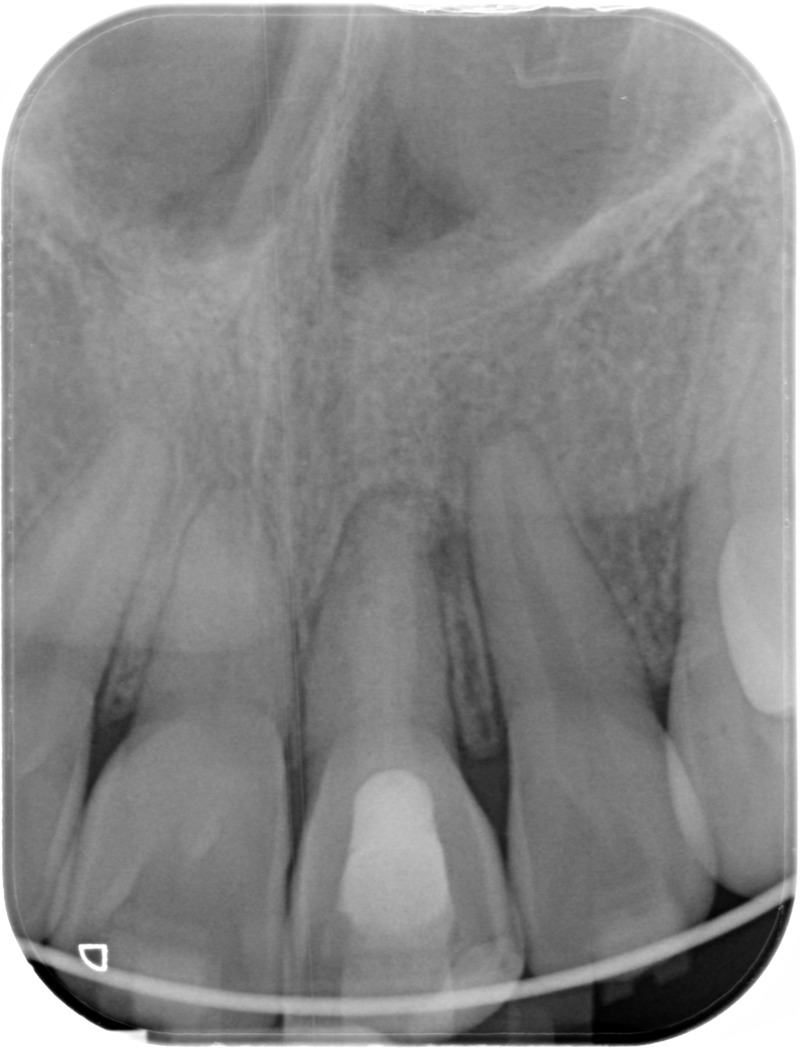

• Traitement endodontique : Sous anesthésie locale et à travers la protection d’un champ opératoire nous accédons à la pulpe de la dent à soigner, puis aux canaux de ses racines que nous devons désinfecter. Ce soin nécessite l’élimination complète de la source de contamination (souvent la carie) parfois sous une ancienne reconstitution ou une couronne qu’il faut alors retirer. Une fois le nettoyage et la mise en forme des canaux réalisés, nous les obturons de façon hermétique avec un ciment et un matériau thermoplastique appelé Gutta Percha. Ceci afin d’empêcher une nouvelle prolifération bactérienne et d’assurer le maintien de la dent dans ses structures de soutien (ligament parodontal et os alvéolaire). L’ouverture effectuée au centre de la dent sera d’abord refermée avec un pansement provisoire avant d’envisager ensemble la reconstitution d’usage : un composite, un inlay-onlay ou une couronne.

Après